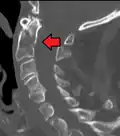

Fractures of the dens are classified into three categories according to the Anderson Alonso system:

- Type I fracture - Extends through the tip of the dens. This type is usually stable.

- Type II fracture - Extends through the base of the dens. It is the most commonly encountered fracture for this region of the axis. This type is unstable and has a high rate of non-union.

- Type III fracture - Extends through the vertebral body of the axis. This type can be stable or unstable and may require surgery.[1]

A fracture of the base of the dens as seen on CT -